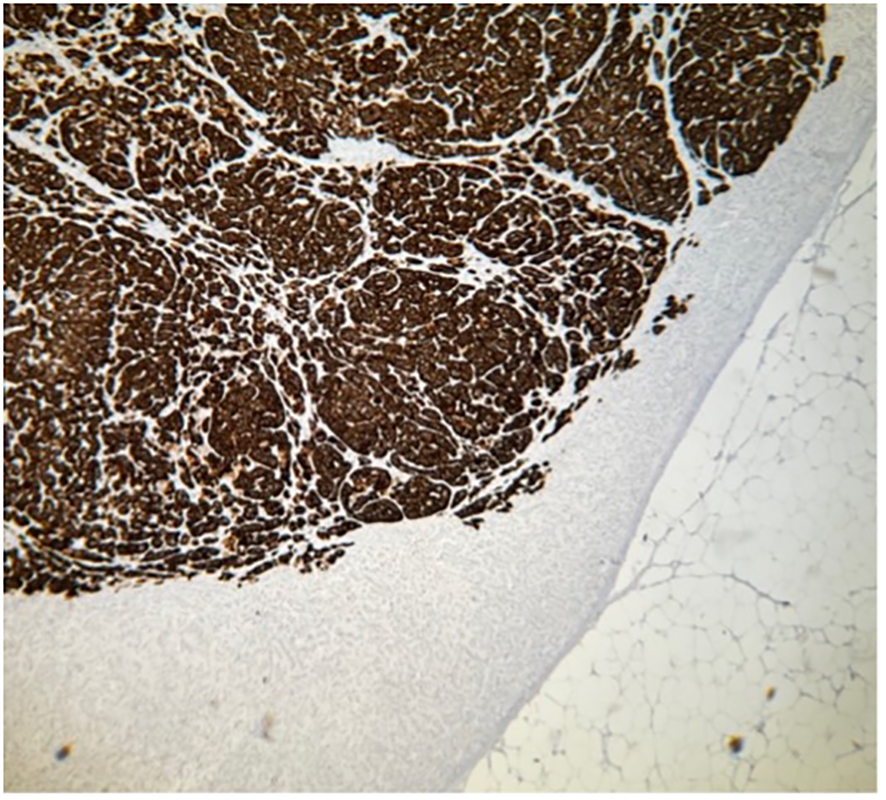

Figure 7

Histopathology of specimen from the adrenal gland in a patient with PA. Part of CYP11B2-negative nodule A, immunohistochemistry demonstrating absent expression of aldosterone synthase, CYP11B2. Magnification ×40.

Consequently, 7–10 out of 14 lateralized cases had some form of nodular disease or true hyperplasia (50%–71%), which supports previous data (31, 38). Assuming that the 31 patients who did not lateralize also had some form of non-APA disease, the total number of patients with non-APA disease approaches 38–41 out of 45 subtype-classified patients with PA (84%–91%). See Figures 4–7 for histological examples of CYP11B2-ICH and its value.